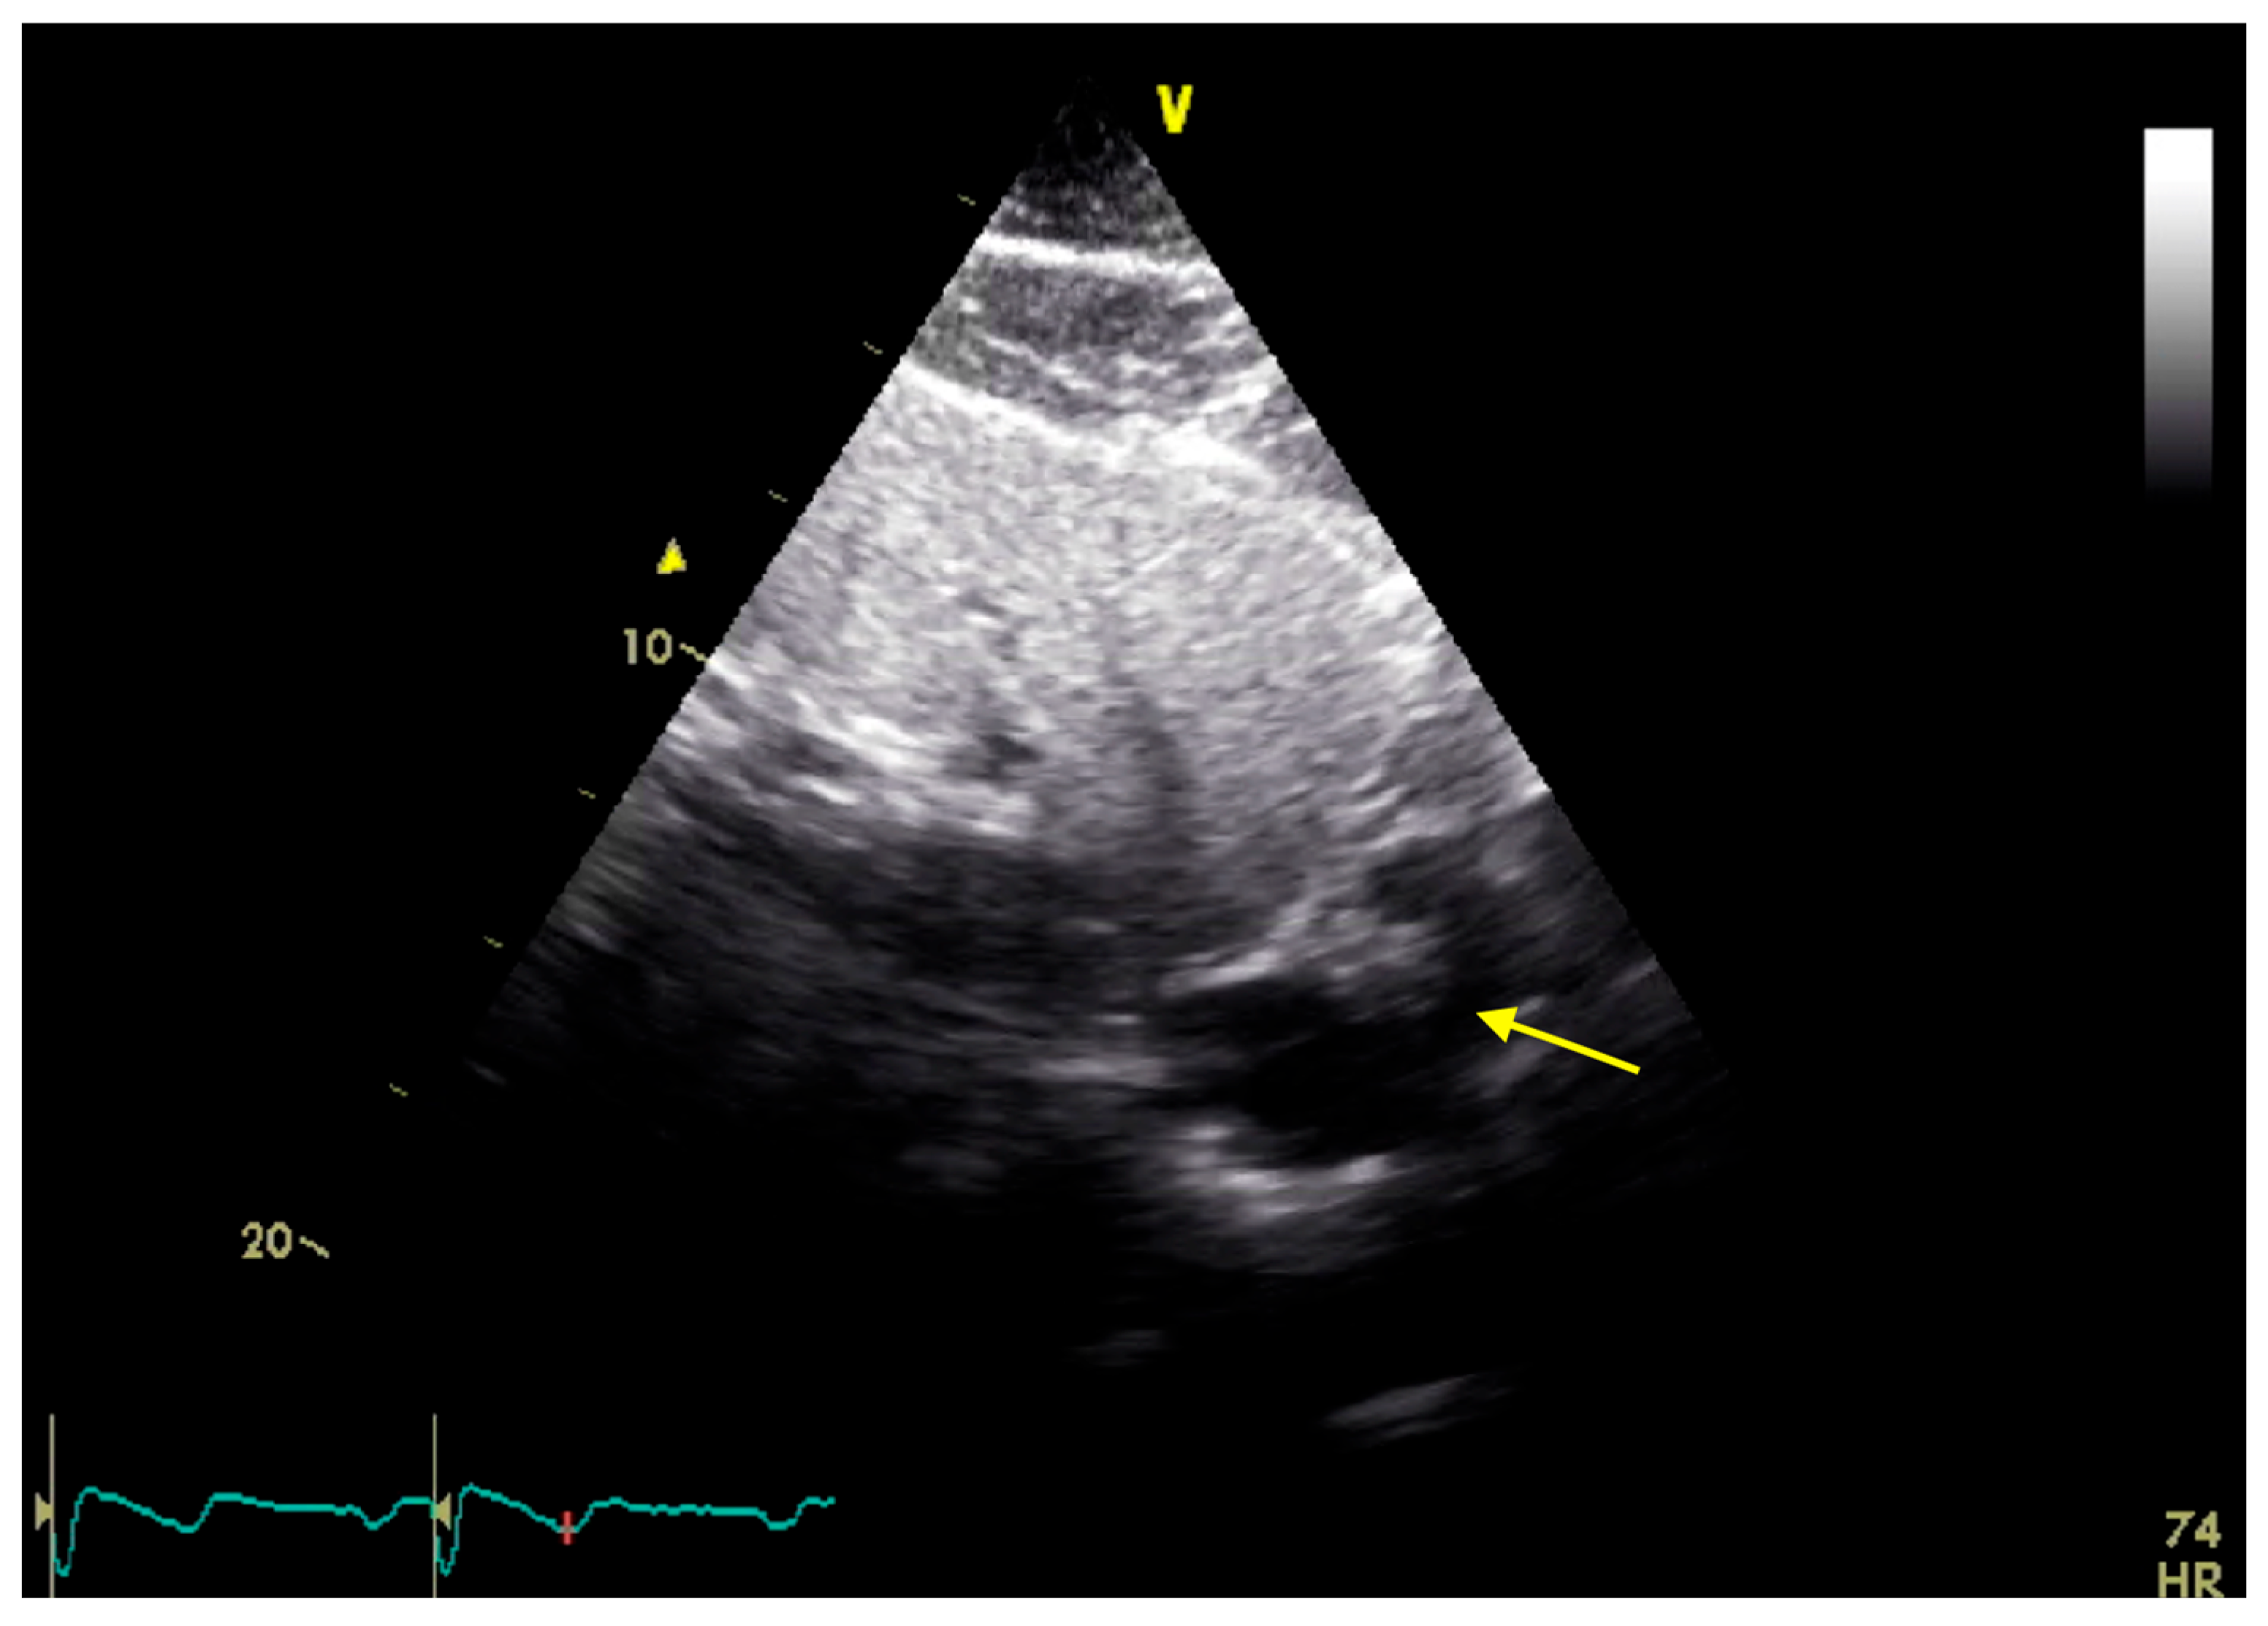

2. Case Presentation